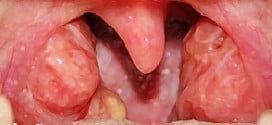

Тонзиллит представляет собой заболевание инфекционно-аллергического характера, при котором воспалительный процесс локализуется в небных миндалинах. Также бывают задействованы близлежащие лимфоидные ткани глотки — гортанные, носоглоточные и язычные миндалины.

Тонзиллит поражает небные миндалины, тем самым вызывая в них воспаление. Относится к группе инфекционных заболеваний, возбудителем которого является вирусная, либо бактериальная инфекция.

Ангина — это инфекционное заболевание, основным проявлением которого является воспаление небных миндалин. Недуг провоцируют различные микробы, главным образом стрептококки, они попадают в глотку чаще с предметами домашнего обихода, которыми пользовался больной ангиной.